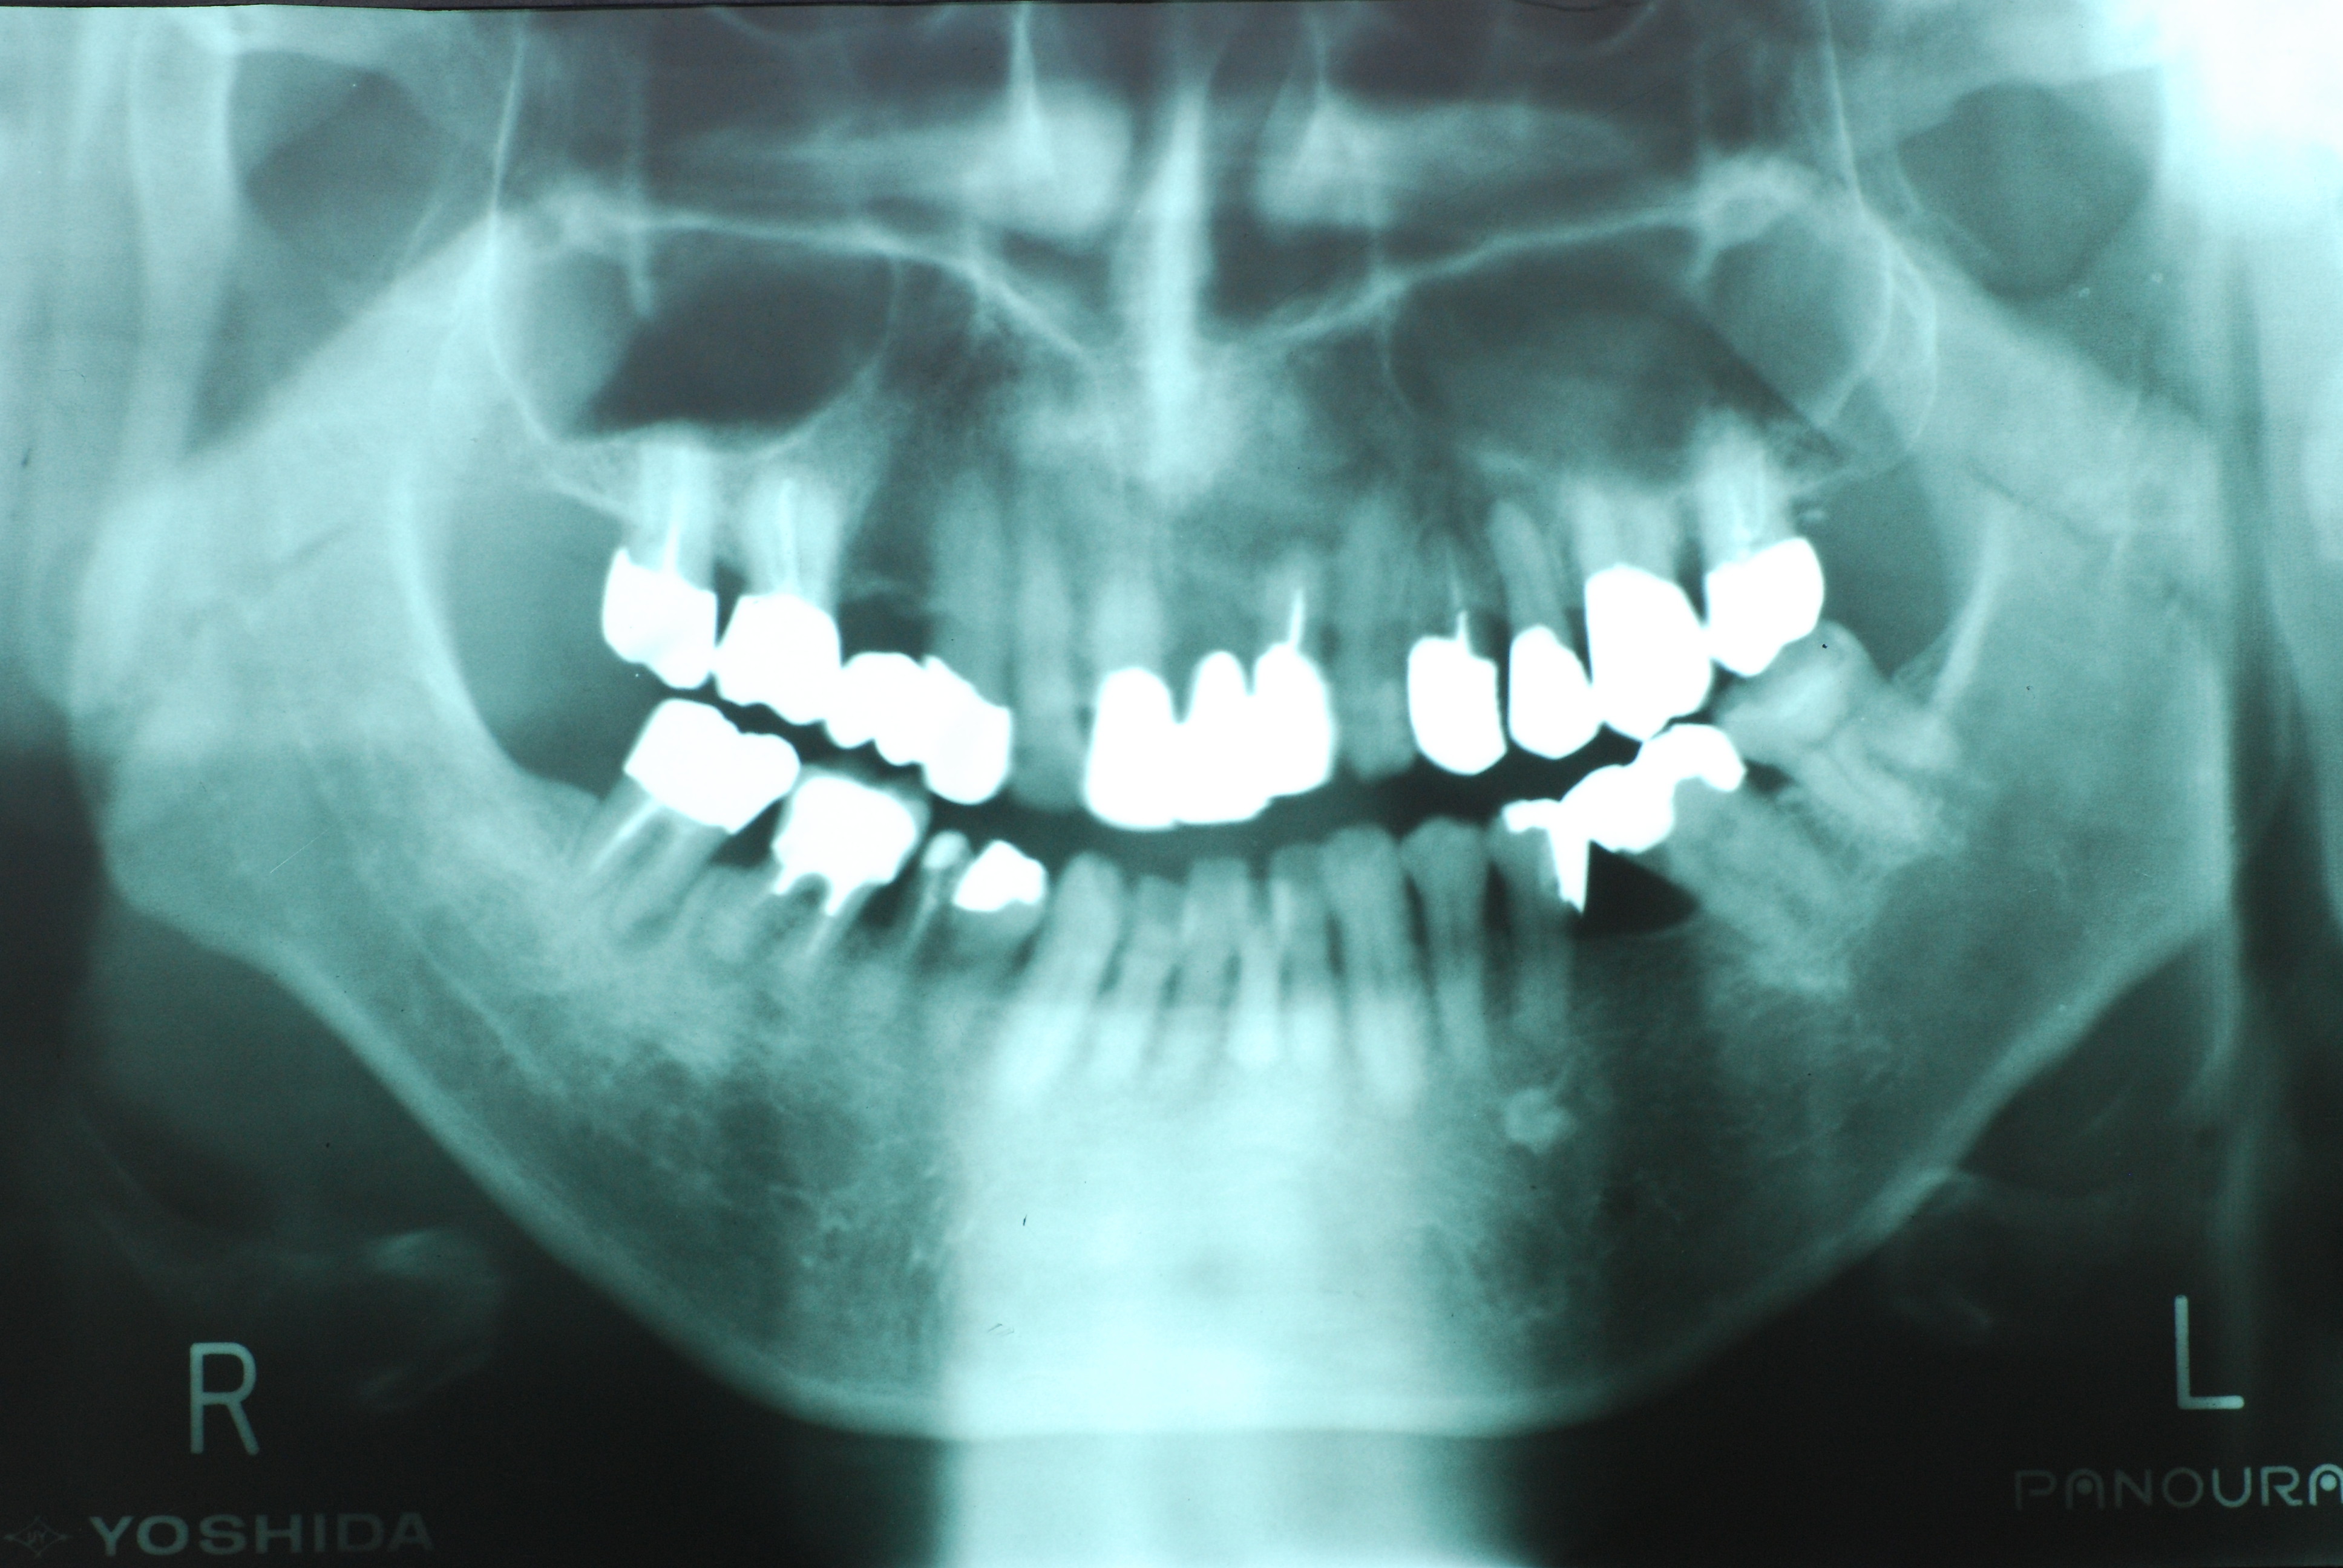

左下の一番奥の歯の治療がいい加減なようです。

そして歯周病を併発していて別の歯科医院で抜くしかないと言われて何とかならないかと当院に来られました。

左下の一番奥の歯の治療がいい加減なようです。しかし治療をしてみると滅菌しながら治療をすることの困難さを痛感しました。

三本ある根管の内、難しい手前の根幹の治療が為されていません。顎の骨に黒い影ができています。

骨の部分は健康を回復しています。影がありません。治療が成功しています。

反対側の大臼歯には分岐部に深い虫歯と深い分岐部病変がありますが、虫歯の治療後は歯周病が酷いのに来られなくなりました。

上のレントゲンでも歯根の間に影があります。悪性の分岐部病変ですね。